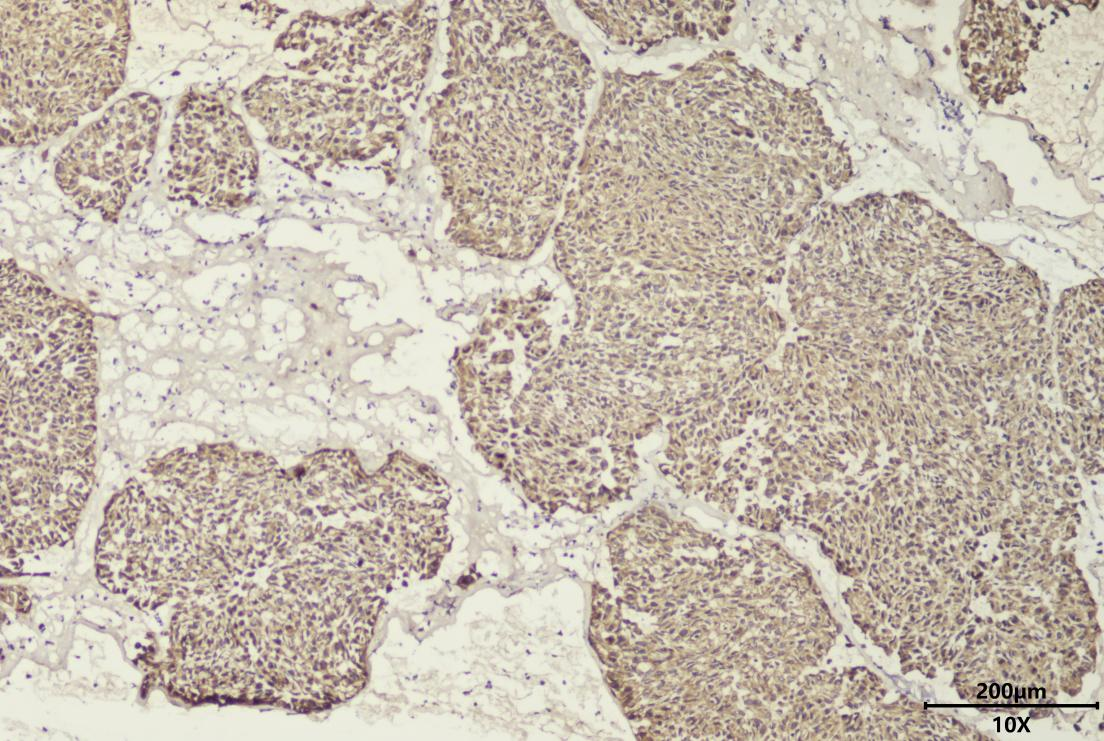

肺神经内分泌瘤术中冰冻TTF1免疫组化染色

比如,在乳腺肿瘤诊断中,该技术通过CK5/6抗体染色清晰标记肌上皮细胞存在状态,直观判断肿瘤是否突破基底膜,为外科医生确定手术切除范围提供明确依据。针对肺部占位性病变,当术中冰冻切片难以明确肿瘤来源时,借助CK(细胞角蛋白)和TTF1(甲状腺转录因子1)染色可精准锁定肺上皮来源肿瘤,成功诊断肺神经内分泌肿瘤、硬化性肺泡细胞瘤等疑难病例,且后续常规病理检查均验证了诊断准确性。